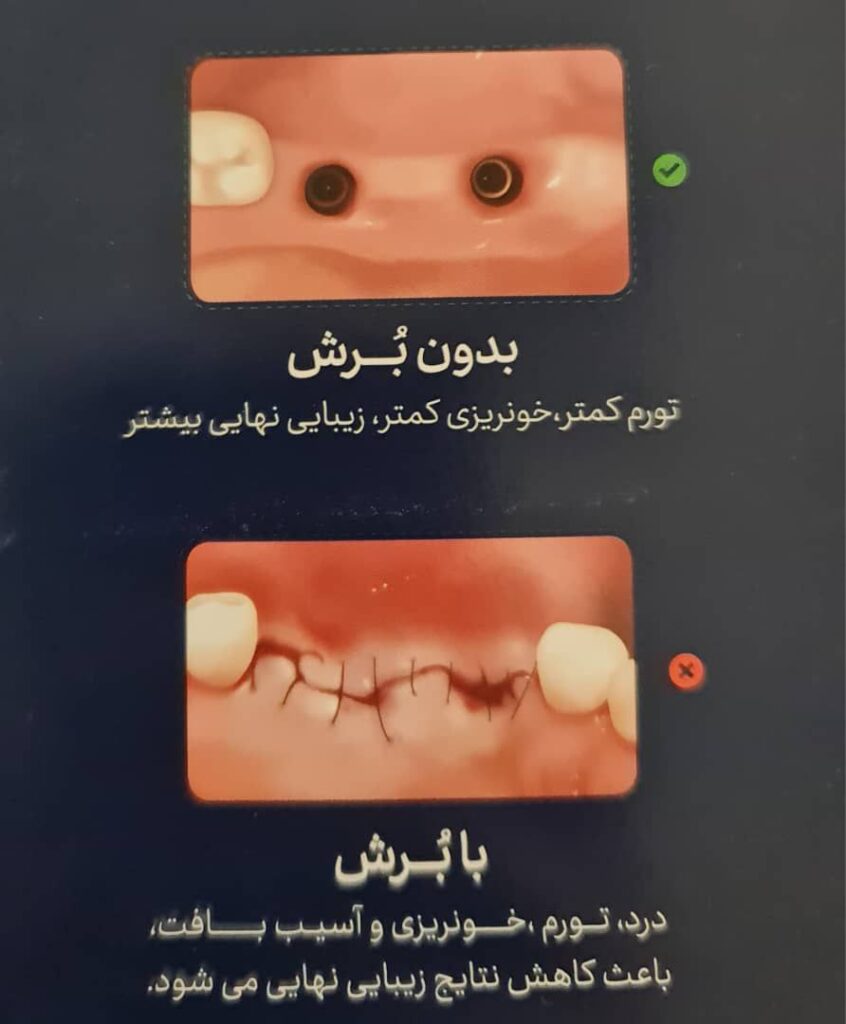

کمترین تهاجم: نیاز به برشهای بزرگ کمتر بوده و ترمیم زخم سریعتر است